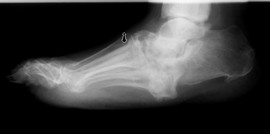

Charcots fod, kronisk

På røntgenbilledet af kroniske Charcots fod ses svære destruktioner og fejlstillinger af knoglerne.